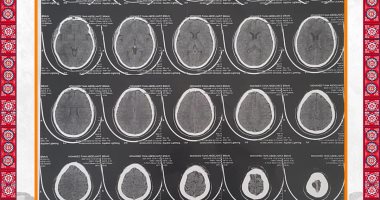

أشعة المريض